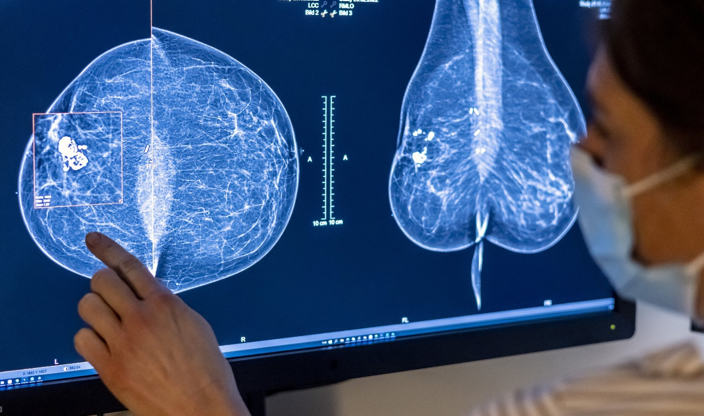

유방촬영술은 같은 사진을 보고도 미세한 병변이 지나갈 수 있다.

검진에서 음성으로 나왔는데, 다음 검진 전 암이 발견되는 경우가 있다는 뜻이다. 이걸 ‘사이암’이라고 부른다.

그래서 1월 29일 《랜싯》에 실린 임상시험 결과가 조용히 눈에 들어왔다.

AI가 판독을 보조했을 때, ‘사이암’이 수년 추적에서 12% 줄었다고 연구진은 보고했다.

“검진 사이에 발견되는 암”이 줄었는지는, 이 기술이 실제로 도움이 되는지 가늠하는 핵심 지표였다.